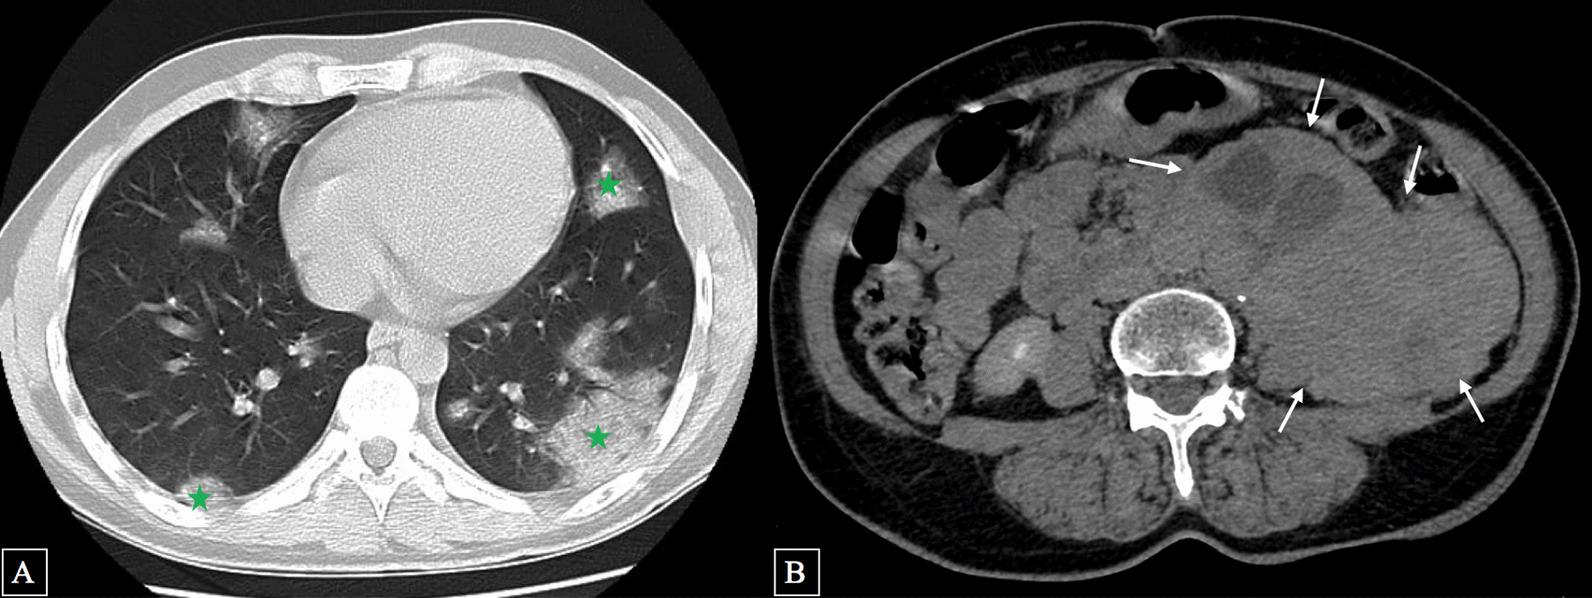

We report the case of a 68-year-old Caucasian woman with an incidental diagnosis of retroperitoneal paraganglioma that was discovered on chest computed tomography performed for high suspicion of coronavirus disease 2019 pneumonia. The patient showed no metastasis and was successfully treated by complete surgical removal of the tumor.

我们报告了一例 68 岁白人女性的病例,她在因高度怀疑 2019 年冠状病毒病肺炎而行胸部计算机断层扫描时偶然诊断出腹膜后副神经节瘤。该患者没有转移,通过成功地完全切除肿瘤进行了治疗。